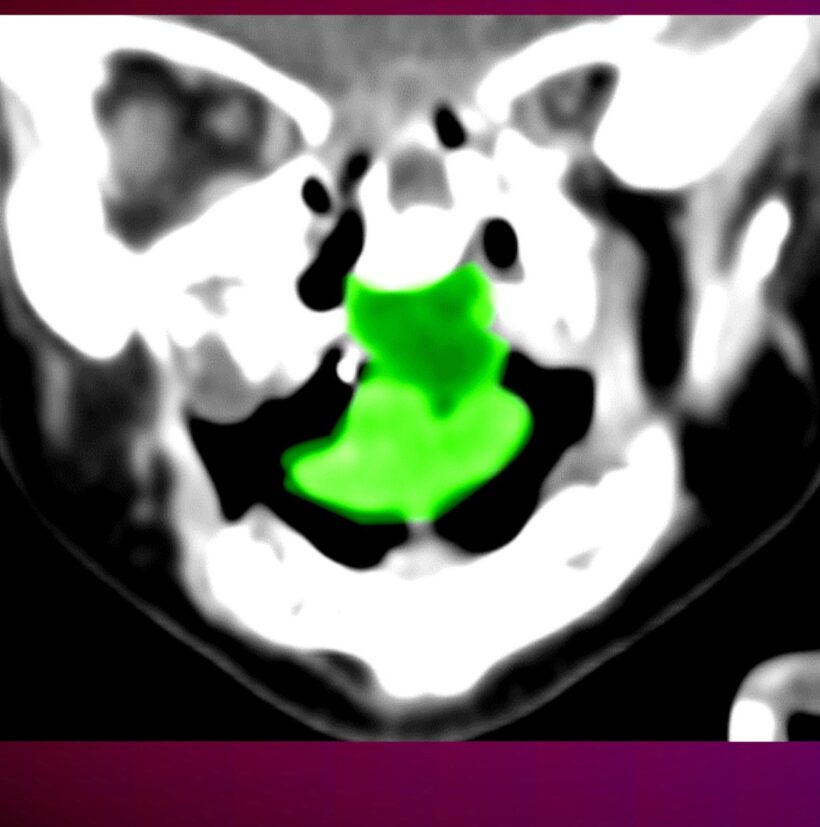

While in utero, baby Yael* developed a rare tumor—only tens of cases have ever been reported in the literature. From birth, her life was in danger, since the tumor obstructed her airway and made oral feeding difficult. After assessing her condition, the physicians at the regional hospital where she was being treated agreed that it was in her best interest to be transferred to Rambam for specialized care. Upon her arrival, she was admitted to the Wagner Green Pediatric Intensive Care Unit in the Ruth Rappaport Children’s Hospital.

The surgery was successful, and Yael spent several days recovering in the pediatric ICU. Dr. Capusha notes that Yael may need further rehabilitative treatment and palate reconstruction. Regarding the cause of the tumor, he explains, “It could be due to a congenital anomaly, genetic disease, a teratogen in the womb, or an unknown source. In any case, worldwide, only dozens of cases are reported annually.”